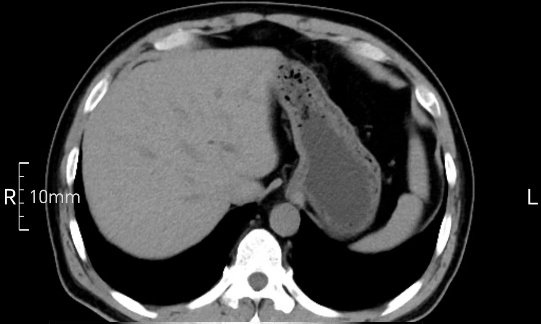

看看下面三幅便知遵醫(yī)囑的重要性。

完美禁食且喝飽飽,胃壁完美展現(xiàn)。

CT檢查前的“禁食”和“喝飽”,看似矛盾,實(shí)則合情合理,分工合作:空腹:是為了讓上腹部(肝膽胰脾腎等)的圖像清晰無(wú)干擾,并保障檢查安全。喝水:有效的充盈胃部和、腸道使圖像清晰呈現(xiàn)。兩者巧妙配合,都是為了給您一個(gè)最精準(zhǔn)的診斷結(jié)果。